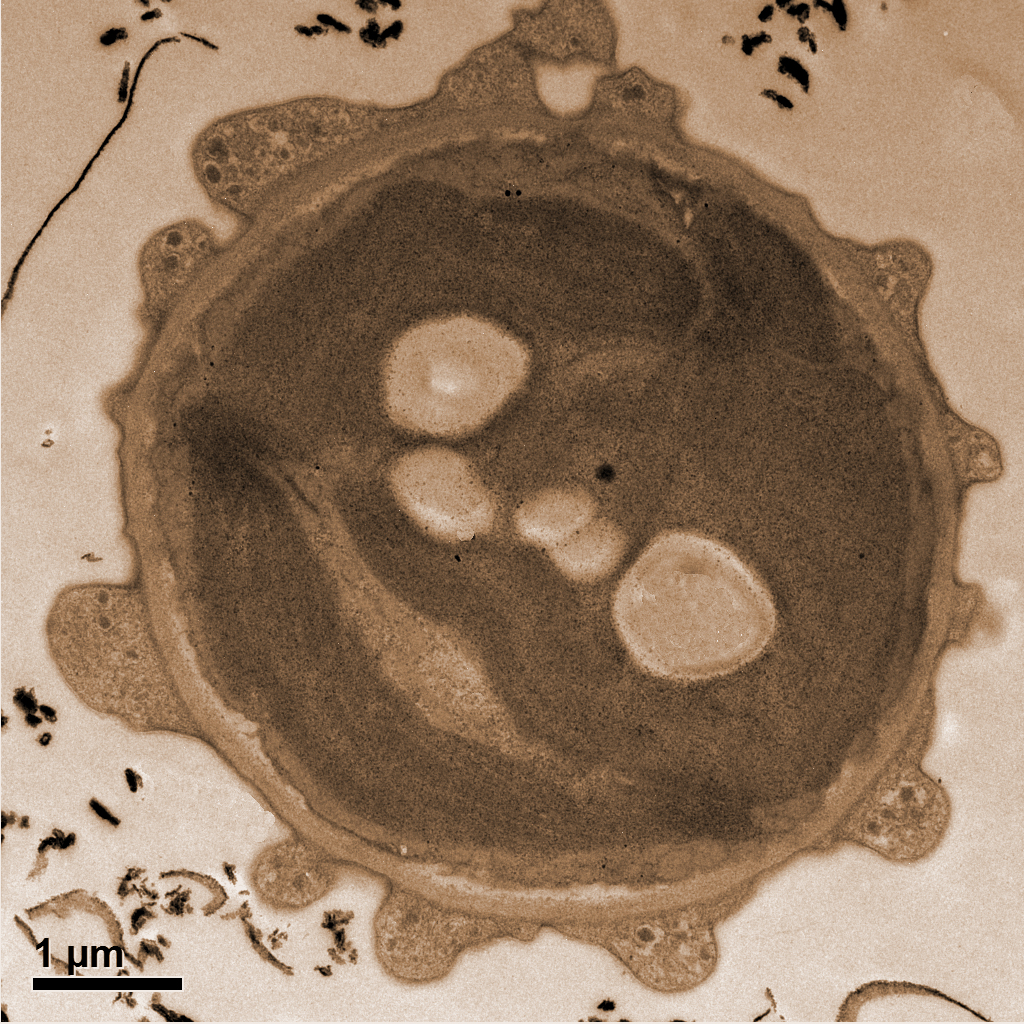

Untersuchung mit tierischen Zellen

Claudia Mayrhofer kam nun im (Forschungs-)Alltag die Idee, stattdessen Kaffee als Kontrastmittel in der Elektronenmikroskopie einzusetzen: „Die Anregung, Kaffee als alternatives Kontrastmittel zu prüfen, entstand aus der Beobachtung, dass eingetrocknete Kaffeereste eine bemerkenswert hartnäckige Färbekraft besitzen und somit Kaffee potenziell für die Kontrastierung biologischer Proben geeignet sein könnte.“ Ein neuer Gedanke, denn bisher wurde Kaffee laut den beiden Expert*innen nicht als Kontrastmittel verwendet. Die beiden Forscherinnen führten anschließend – gemeinsam mit Masterstudent Robert Zandonella – Untersuchungen durch. Ilse Letofsky-Papst und Claudia Mayrhofer: „Nachdem erste Versuche an Algen vielversprechend waren, haben wir die Thematik im Rahmen einer Masterarbeit systematisch untersucht. Wir behandelten dabei Schnitte der Zebrafischzellen mit Kaffee sowie verschiedenen handelsüblichen Ersatzprodukten. „Als Ersatz für Uranylacetat gelten Lanthanidensalze wie Samarium- Triacetat oder Gadolinium-Triacetat (UAR-EMS, Uranyless)“, erklären die Expertinnen. Mittels Transmissions-Elektronenmikroskopie detektierte Robert Zandonella die Mitochondrien in den Zellen und quantifizierte den durch die verschiedenen Färbemittel erzielten Kontrast. Dabei zeigte sich, dass Kaffee eine sehr gute Kontrastierung ermöglicht. Noch bessere Kontrastwerte erzielte die ebenfalls getestete Chlorogensäure, ein Hauptbestandteil von Kaffee.“ Am Institut für Elektronenmikroskopie und Nanoanalytik der TU Graz (FELMI-ZFE) ist es aus ethischen Gründen nicht möglich, an menschlichen Zellen zu forschen, daher können die Forschenden dort nur Untersuchungen an tierischen Zellen durchführen. „Bisher wissen wir, dass die Kaffee-Kontrastier-Methode für Zellwände in Mäusen und Zebrafischen funktioniert. Weitere Untersuchungen sind geplant, um die Anwendbarkeit systematisch zu prüfen. Für einen Einsatz in der medizinischen Diagnostik liegt jedoch noch ein weiter Weg vor uns, da hierfür sehr strenge Zulassungs- und Prüfverfahren bestehen.“